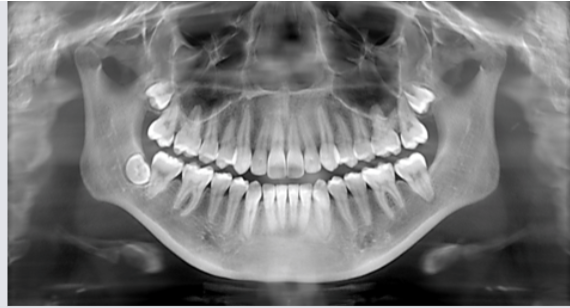

what does panoramic xray show

A wide view of the maxilla, mandible, and pts overall oral and facial structure

what is panoramic xray used to evaluate

dentition and supporting structures

impacted teeth

eruption patterns, growth, and development

disease lesions and conditions of the jaw

trauma